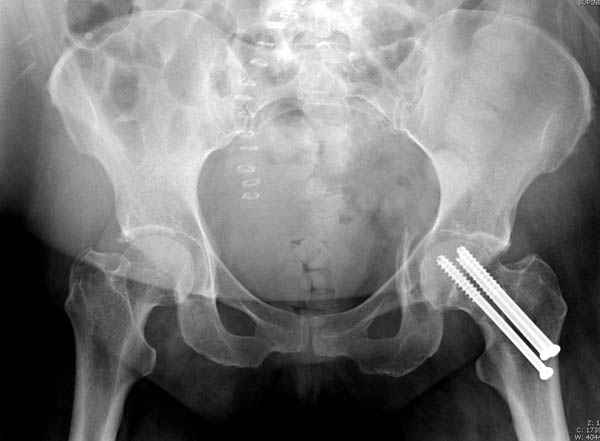

В данный момент скелетное вытяжение поучается через перелом шейки, а фиксированный перелом шейки будет участвовать в процессе вытяжения через каннюлированные шурупы.

Перелом шейки смогли зафиксировать через пару дней, ацетабулум до сих пор не оперирован, на вытяжении.